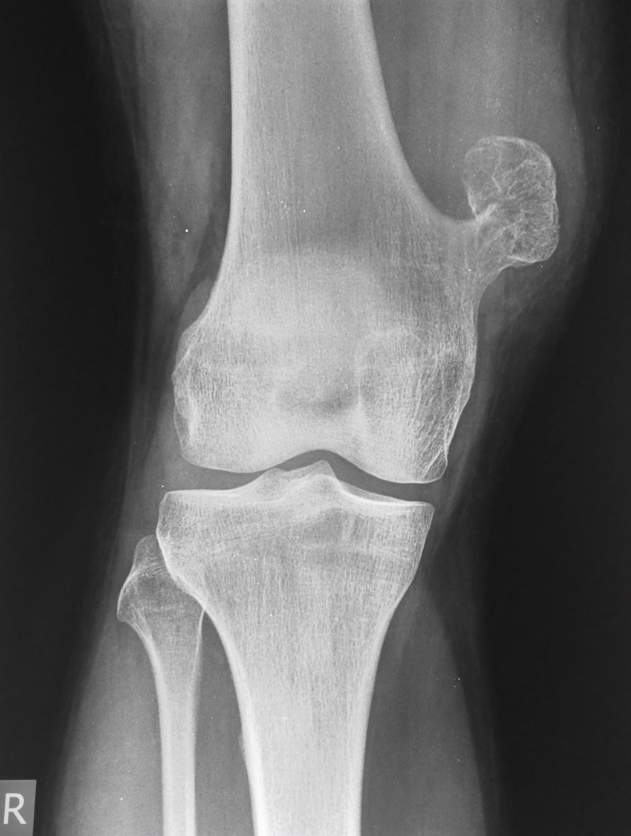

Osteochondromas